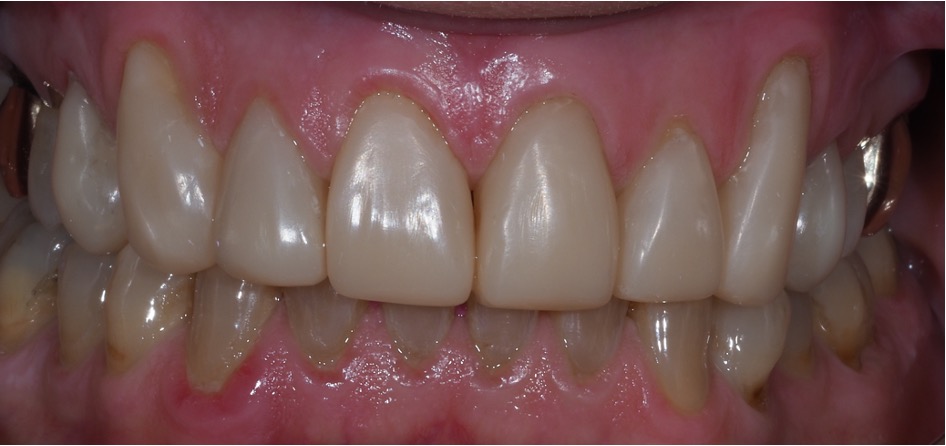

Direct composite is often used to treat toothwear. It is a minimally invasive method that does not damage the underlying tooth structure. It can chip, stain and fail. However, replacement and repair is more straightforward. This case was treated with direct composite alone.

Another case of mild toothwear and discolouration was treated with direct composite bonding.